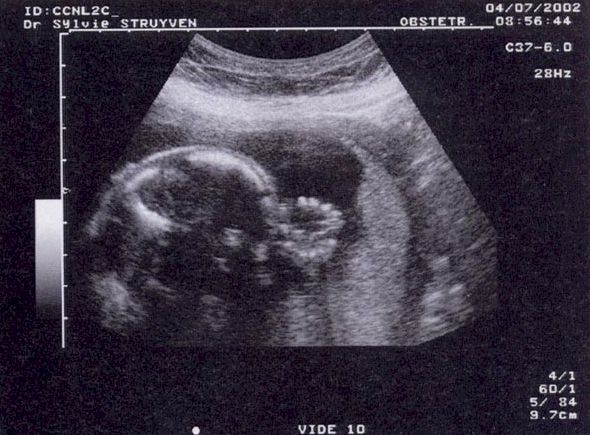

2nd Echographie obstétricale -

© www.mottaghian.net